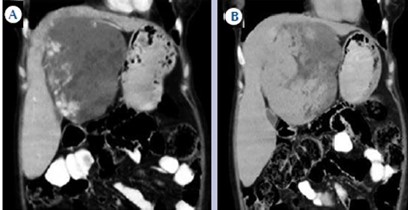

Hepatocarcinoma fibrolamelar

El carcinoma fibromelar hepatocelular es poco frecuente y representa menos de 1% de todos los casos. Se presenta principalmente en adolescentes y adultos jóvenes como una masa tumoral hepática única, con frecuencia de gran tamaño, sin asociación con cirrosis y rodeada de una cápsula fibrosa. En la tomografía multicorte, sin contraste, se observan tumores hipodensos heterogéneos con una cicatriz central muy hipodensa. También puede haber áreas de necrosis y calcificaciones. Son lesiones hipervasculares con captación intensa pero heterogénea (Anexo 15) del medio de contraste en fase arterial, la captación en fase portal y de equilibrio son variables y la cicatriz central, los septos y la cápsula del tumor son hiperdensos en fase tardía, incluyendo en los estudios de RM.(18-19)